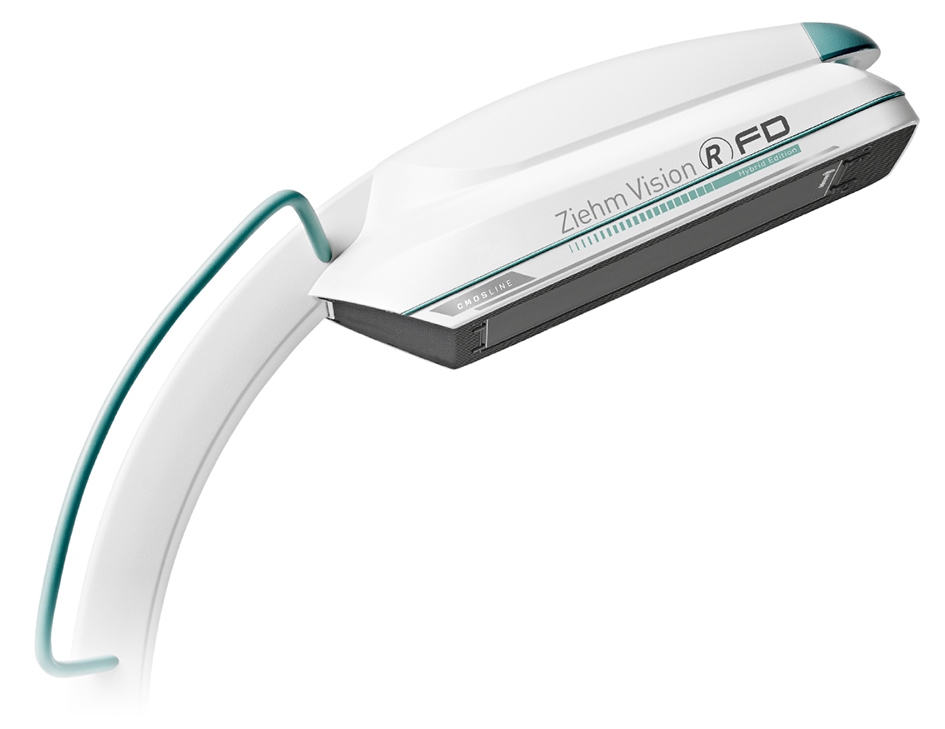

Ziehm Vision RFD Hybrid Edition

Мобільний ангіограф Ziehm Vision RFD Hybrid Edition

Мобільний ангіограф Ziehm Vision RFD Hybrid Edition виробництва компанії

Ziehm Imaging GmbH – унікальне мобільне багатофункціональне гібридне рішення найвищого класу з моторизацією по 4-х осях та ізоцентричним рухом, яке не потребує спеціального переобладнання операційної та готове до роботи в будь-який час і практично в будь-якому місці.

Завдяки рентгенівському генератору потужністю 25 кВт або 30 кВт, різноманітному програмному забезпеченню та функцій оптимізації зображення одночасно з мінімізацією дози, мобільний ангіограф Ziehm Vision RFD Hybrid Edition може використовуватися в широкому діапазоні: від кардіосудинної хірургії і розширеного гібридного використання (коронографія, аневризма абдомінальної аорти, ЧТКА, імплантація серцевих клапанів і кардіостимуляторів тощо) до нейрохірургії та використання в якості традиційної операційної С-арки. Він дає можливість отримувати високоякісні рентгенівські знімки, які до цього можна було отримати тільки у випадку використання стаціонарних ангіографічних систем.

Мобільний ангіограф Ziehm Vision RFD Hybrid Edition виробництва компанії Ziehm Imaging GmbH – унікальне мобільне багатофункціональне гібридне рішення найвищого класу з моторизацією по 4-х осях та ізоцентричним рухом, яке не потребує спеціального переобладнання операційної та готове до роботи в будь-який час і практично в будь-якому місці.

Мобільний ангіограф Ziehm Vision RFD Hybrid Edition виробництва компанії Ziehm Imaging GmbH – унікальне мобільне багатофункціональне гібридне рішення найвищого класу з моторизацією по 4-х осях та ізоцентричним рухом, яке не потребує спеціального переобладнання операційної та готове до роботи в будь-який час і практично в будь-якому місці.  Цифрові плоскопанельні детектори з технологією CMOS розмірами 20,5х20,5 см або 31х31 см з більш високою роздільною здатністю завдяки меншому розміру пікселів у поєднанні з більш низьким рівнем шуму і більш високою швидкістю зчитування.